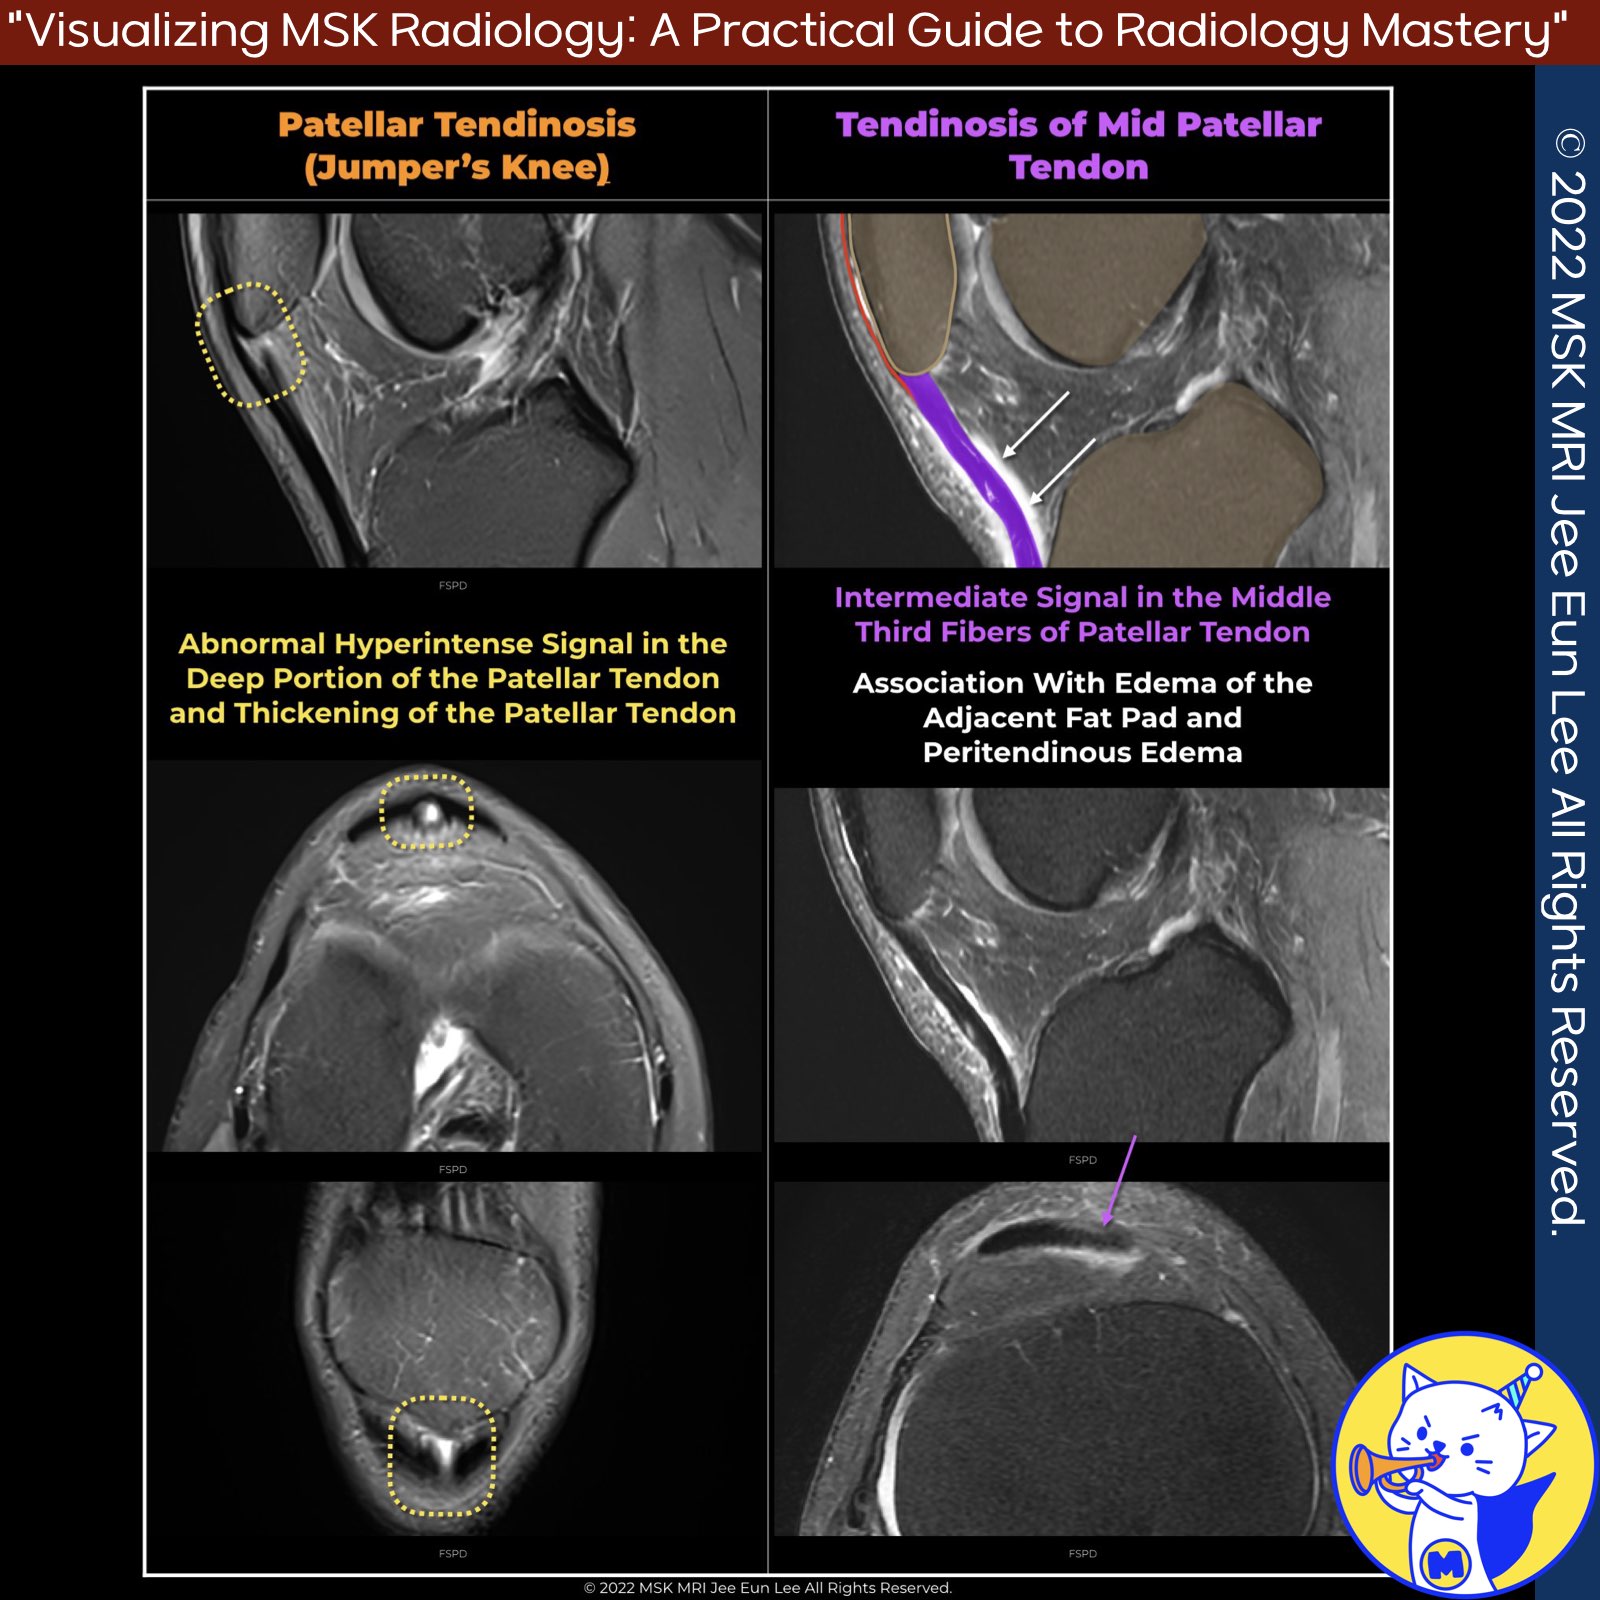

📌 Patellar Tendinosis

- Patellar tendinosis, also known as jumper's knee, is a common disorder affecting the patellar tendon, particularly in young, active individuals.

1️⃣ Acute Patellar Tendinosis

In acute cases, symptoms last for less than two weeks. MRI findings include:

- Increased signal intensity on fluid-sensitive images

- Tendon indistinctness and thickening

- Enhancing regions indicating neovascularity, inflammation, granulation tissue, and fibrosis

- Osseous abnormalities at the inferior patella, including enthesopathy and marrow edema

- Indistinct posterior tendon border and edema in Hoffa's fat pad

2️⃣ Chronic Patellar Tendinosis

Chronic cases, with symptoms lasting more than six weeks, show:

- Thickening and abnormal signal in the entire tendon on T1 and T2-weighted sequences

- Periosteal reaction along the patella

- Calcification within the tendon

- Elongation of the inferior patellar pole

- Diffuse tendon thickening or enlargement in severe cases